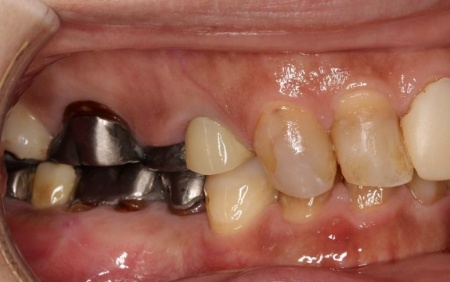

拝見したところ、もともと左上の歯と左下前歯が欠損しているうえ、奥歯の欠損も進んでいたため、噛み合わせが低くなっていました。

また、下の歯は歯根だけが残る「残根」もあり、全体的に噛み合わせが不安定です。

さらに食いしばりの習慣があることから、残っている歯や顎関節に過度な負荷がかかっていると考えられます。

このまま放置すると、食いしばりによる歯の破折や欠損の増加、顎関節への負担増大、前歯の突出の進行などのリスクがあるため、早急に治療を開始する必要があると診断しました。

下顎は残根も利用しながら、矯正用の小さなネジ「テンポラリーインプラント(インプラントアンカー)」を顎の骨に埋め込んで固定源とする方法も併用し、歯を移動させました。